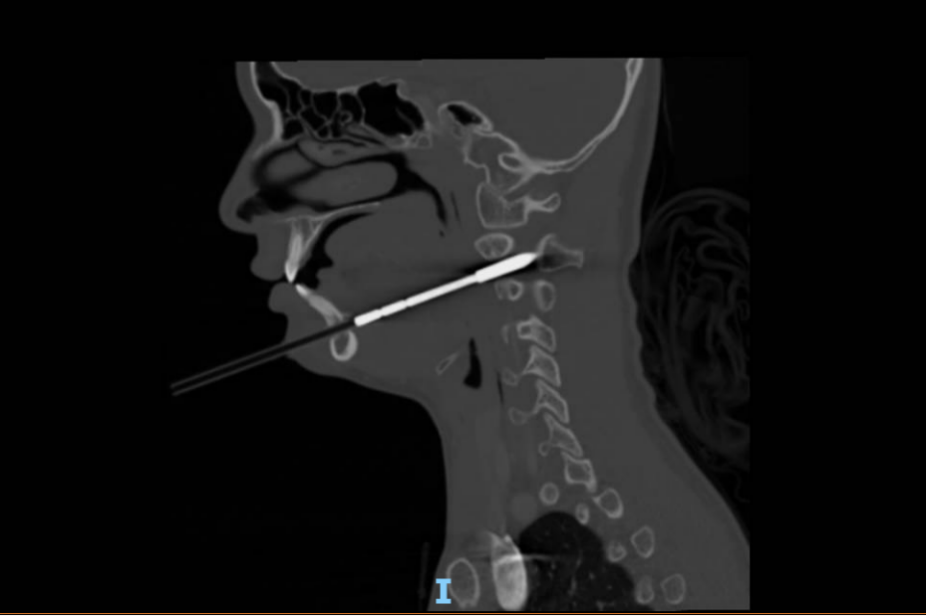

6月2日凌晨,娜娜在父母和教練的陪伴下,緊急抵達北京兒童醫院急診。首診的急診內科戴國瑞醫師迅速對娜娜的病情進行了全面評估。盡管娜娜的生命體征平穩、神志清楚,肢體活動和感覺也未見異常,但CT影像結果卻揭示傷情的復雜性:箭矢穿通了下頜骨和右側頸2椎體,累及椎管,橫突孔內緣骨質可疑受累,且箭頭尖段進入椎管長度約12毫米,右側咽旁間隙受累,局部氣道向左側偏移。

箭矢必須取出,但如何取出才能最大程度降低對孩子的損傷呢?在獲得明確的影像學資料后,戴國瑞醫生立即將娜娜的情況上報了醫務處,在醫務處的支持下,迅速牽頭組織急診外科、骨科、口腔科、耳鼻咽喉頭頸外科等多學科團隊(MDT)進行緊急會診,快速制定了詳細的治療方案:決定立即手術,實施頜面部異物取出術。

6月2日凌晨2時,娜娜被送入手術室。經驗豐富的麻醉科醫生在頸部制動、張口受限的復雜情況下,成功完成了氣管插管,為這場牽動人心的手術奠定了良好基礎。麻醉完成后,耳鼻咽喉頭頸外科副主任醫師劉悄吟對娜娜的口咽部進行了術前探查,發現多處淤青、水腫和軟組織陳舊出血。隨后,骨科副主任曹雋主任醫師和口腔科副主任醫師陳卓合力進行異物拔除。他們首先穩定患兒頭部,用大力鉗夾住箭桿末端,緩慢拔出。起初阻力較小,但箭頭退至下頜骨部位時,阻力明顯增加。兩位醫生憑借精湛的技藝和沉著冷靜的心態,在確保患兒生命體征平穩的前提下,加大了拔出力量。最終,深深扎在下頜骨里的箭矢被完整取出!術后再次用喉鏡探查,確認無活動性出血。